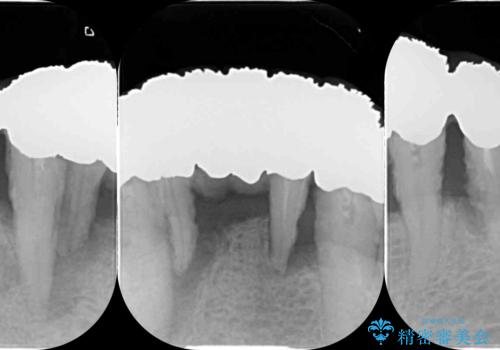

歯周組織検査・X線写真検査の結果、重度歯周病であることがわかりました。

残すことのできない歯を抜去し、入れ歯になることを回避すべくブリッジ治療を行いますが支台となる歯の歯周病を改善すべく歯周病により溶けた歯槽骨の再生治療を計画します。